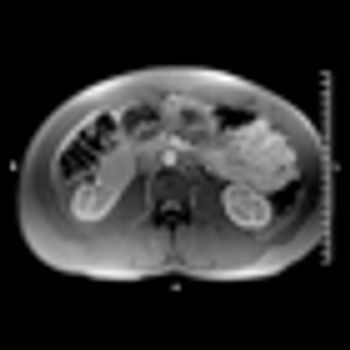

Tumor shrinkage is a valid indicator of response to VEGF inhibition among patients with metastatic renal cell carcinoma when evaluated by a single radiologist observer.

Image-guided radiofrequency ablation may be an effective alternative treatment for small renal cell carcinoma tumors, according to the results of a recent study.